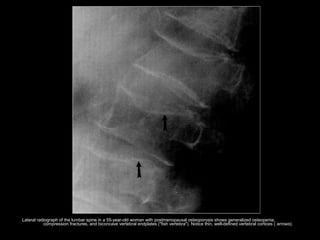

• Fractures - vertebral deformities, which

are also common, include biconcave

end plates (fish vertebrae) and anterior

wedging.

Lateral radiograph of the lumbar spine in a 55-year-old woman with postmenopausal osteoporosis shows generalized osteopenia,

compression fractures, and biconcave vertebral endplates ("fish vertebra"). Notice thin, well-defined vertebral cortices ( arrows).